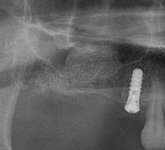

Figure 3D The site 6 months after surgery, confirming integration. Figure 4A Preoperative radiograph showing ridge resorption.

Figure 4B Radiographic confirmation of graft confinement and incremental addition.

Figure 4C Radiographic view of implant placed simultaneously with sinus bone grafting in site No. 3. Figure 4D Radiographic confirmation of the re-establishment of the sinus floor. Figure 4E Final implant-supported restoration.